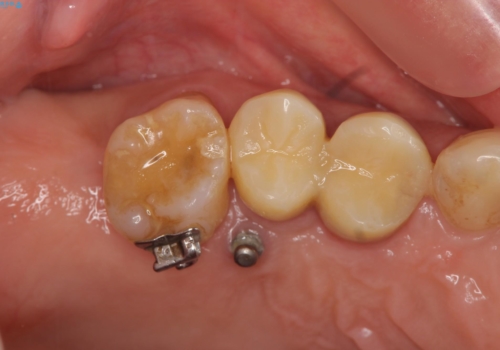

連結補綴について

特定の歯に強く力がかかりまた歯周病により臨床歯根が短くなっているような場合、歯の動揺を抑えるため連結補綴が検討されます。

歯の動揺が続くとより周囲の骨を失い最終的には歯を喪失してしまう可能性が高くなってしまうためです。

今回連結補綴を行うにあたり、歯周病の問題を解決するために再生療法・歯周ポケット除去手術を、またより歯の神経を保存し力に対抗できる環境を整えるために小矯正を行い精度の高いメタルボンドクラウンを製作することができました。